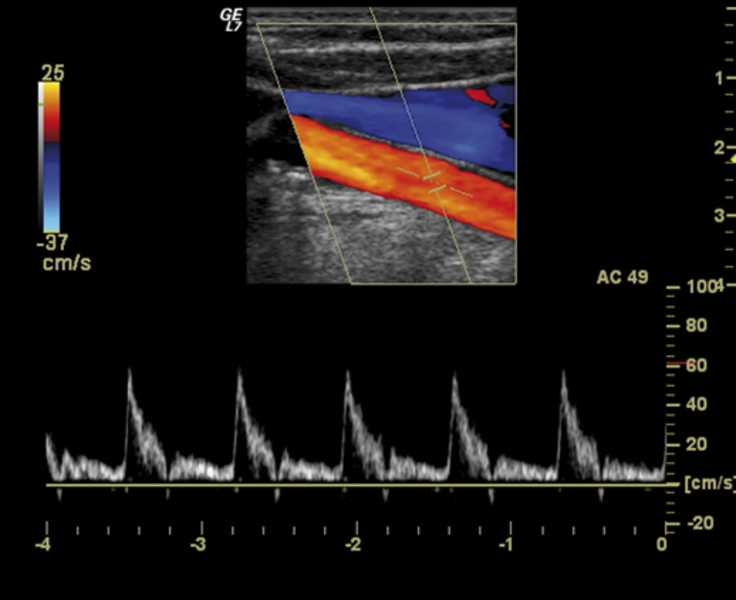

Con l'evento, che si rivolge a medici radiologi, provenienti da tutta Italia, che intendono approfondire le loro conoscenze sull’argomento, si esamineranno i vari distretti corporei (collo, arti superiori ed inferiori, addome) e vi sarà anche una sessione dedicata ai trapianti di fegato e rene.

I vari docenti (Leo, Pollice, Maiorano, Nemore, Quinto, Saponaro), dopo le rispettive relazioni, svolgeranno esercitazioni pratiche su pazienti, invitati per l’occorrenza, utilizzando apparecchiature ecografiche di ultima generazione, sia recentemente acquistate dall'Asl, sia fornite per l’occasione da aziende del settore.